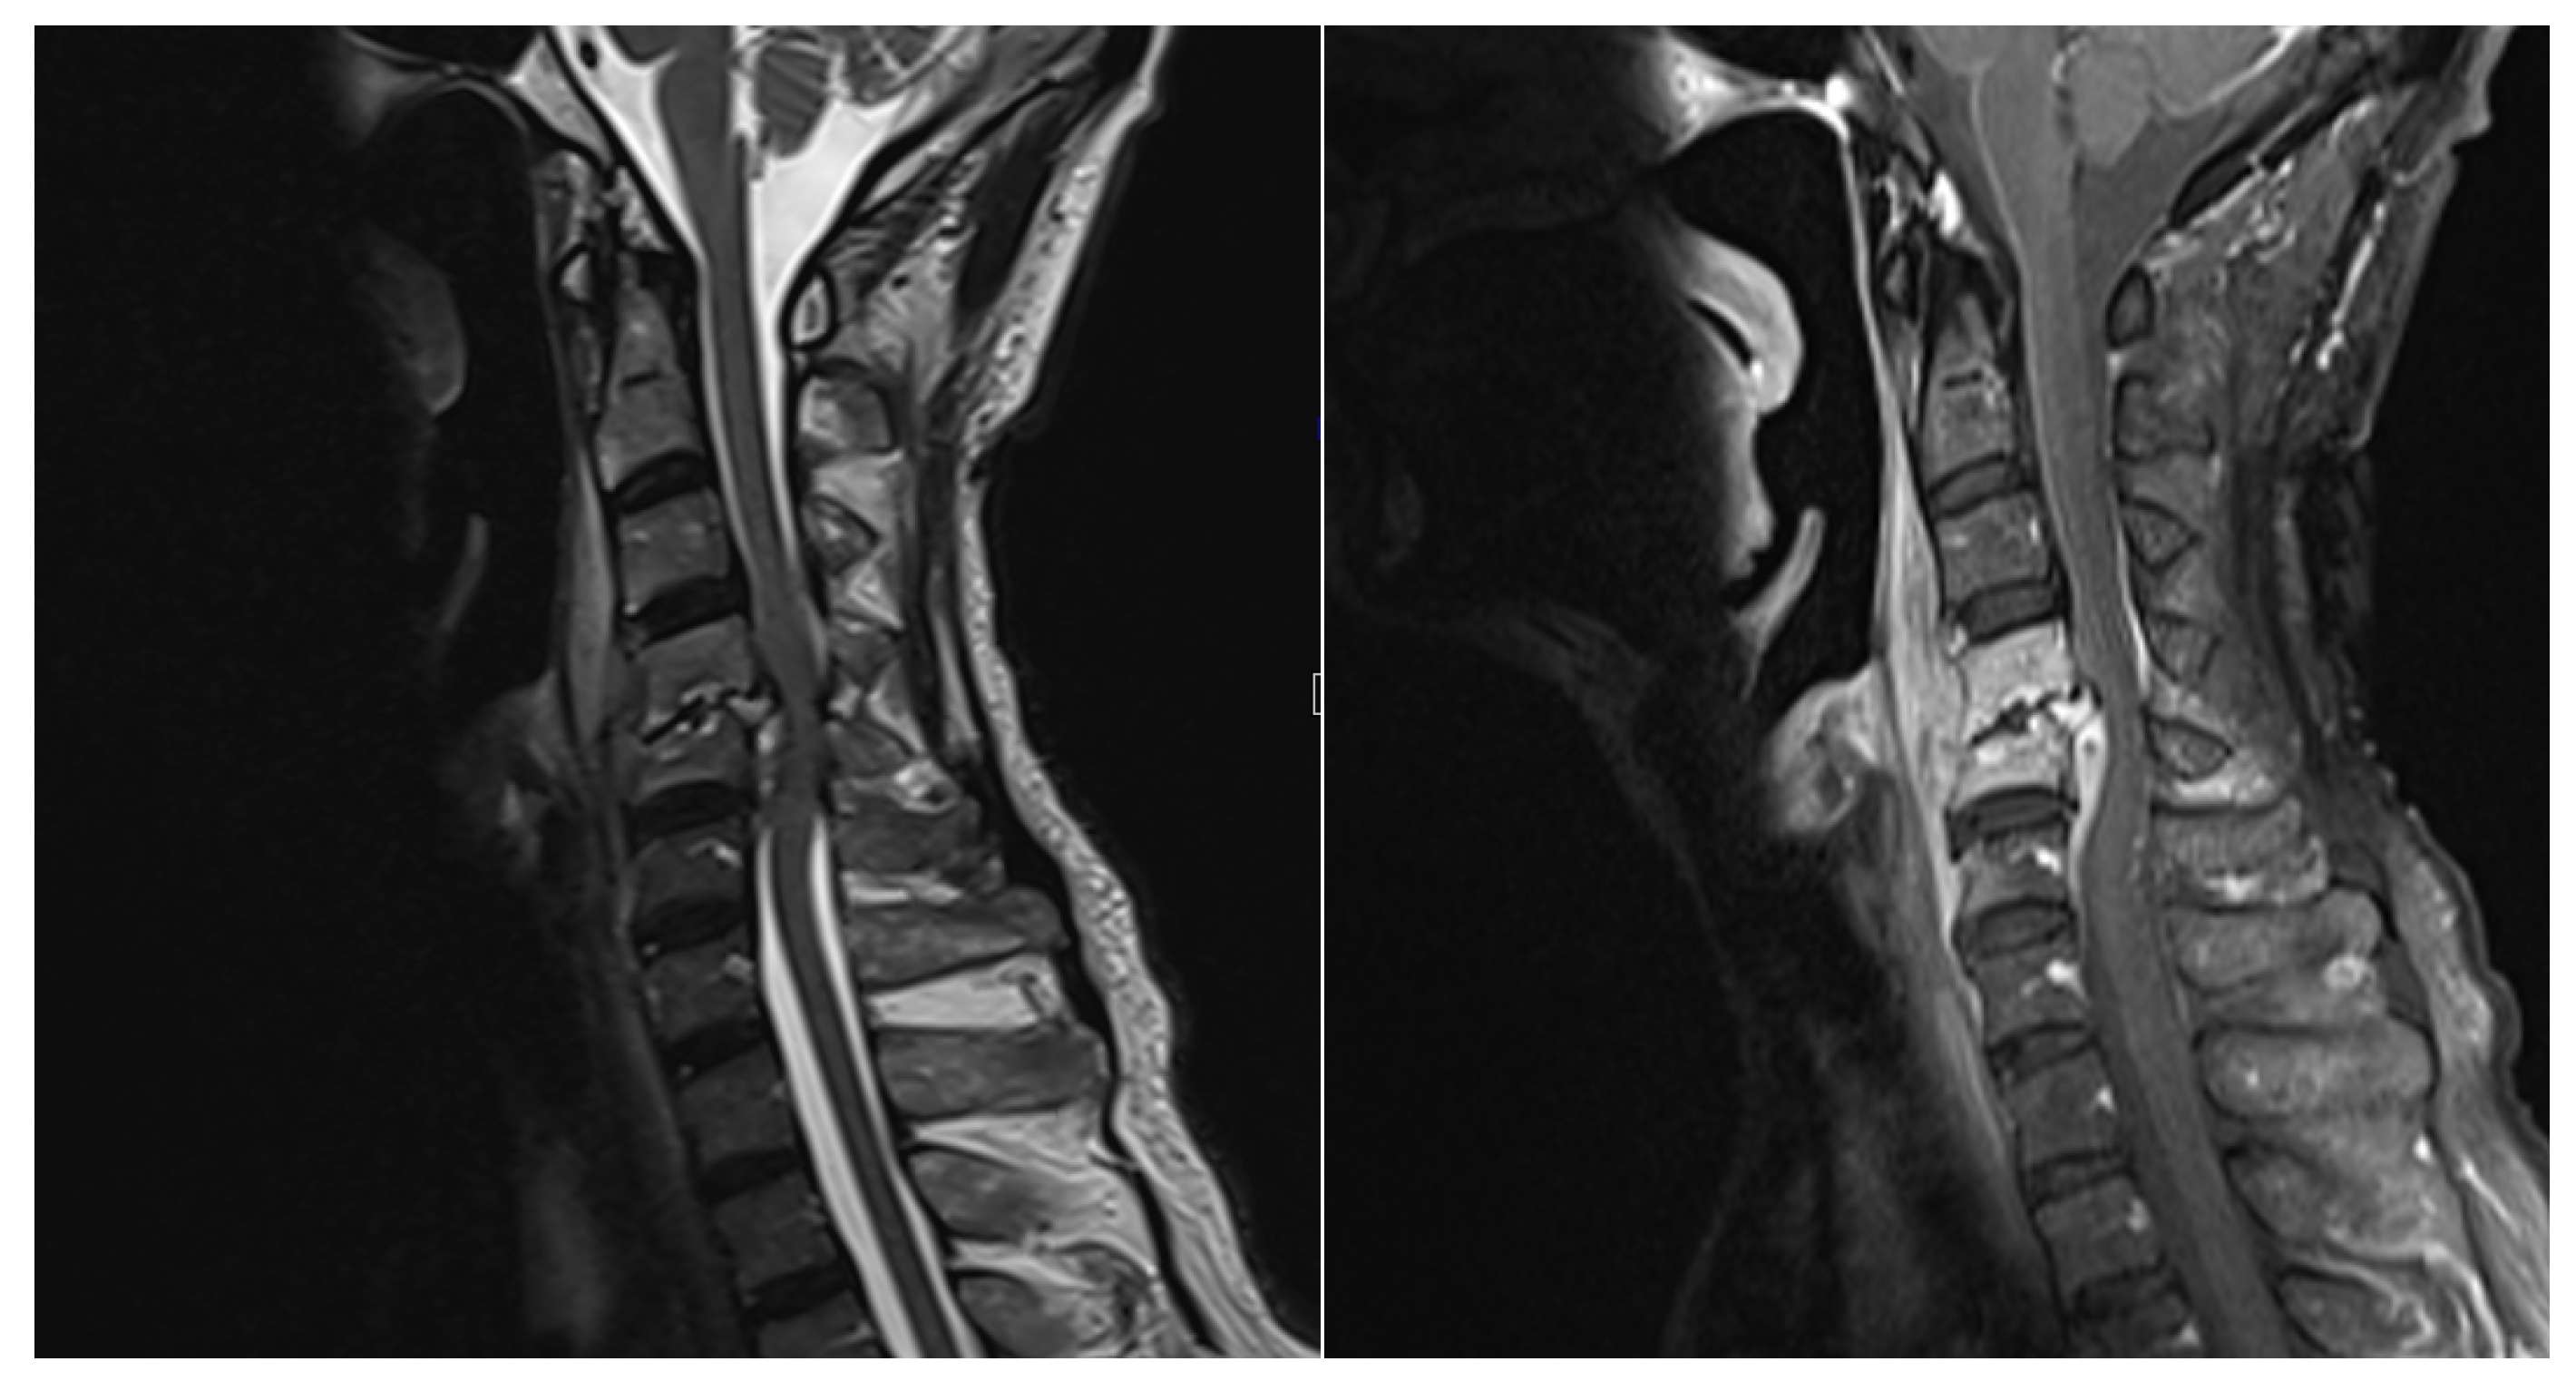

Figure 2. T2 weighted and T1 weighted with contrast MRI showed C5 compression fractures and bone marrow edema and increased paravertebral soft tissue at the C4-5 level has resulted in spinal canal stenosis and compression of the spinal cord.